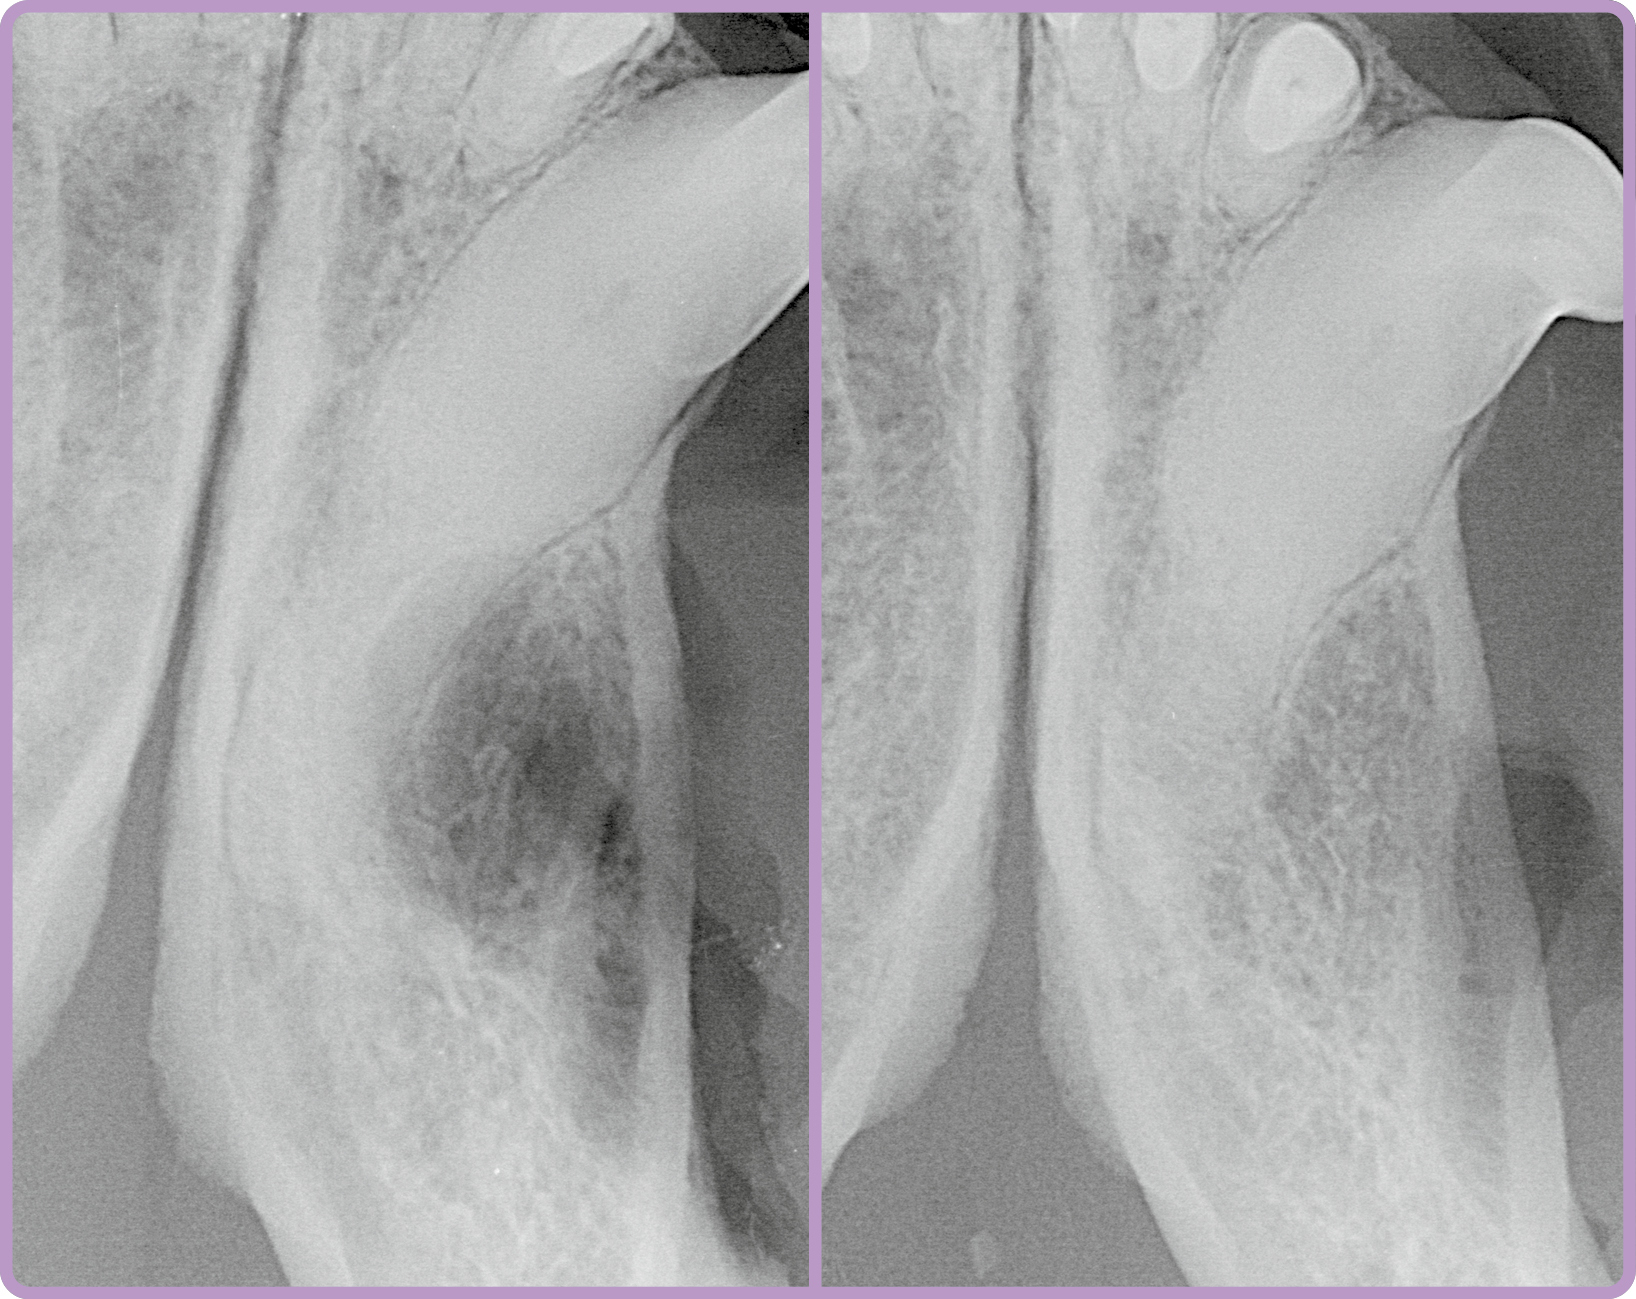

Die Röntgenbefunde nach der Operation zeigen den Zustand nach Extraktion des retinierten Zahns mit dem beteiligten zweiten Prämolaren und unter Kürettage der Knochenzyste unmittelbar im Anschluss der OP sowie nach sechs Monaten (Abb. 2). Sechs Monate nach der OP ist eine progressive knöcherne Durchbauung erkennbar.